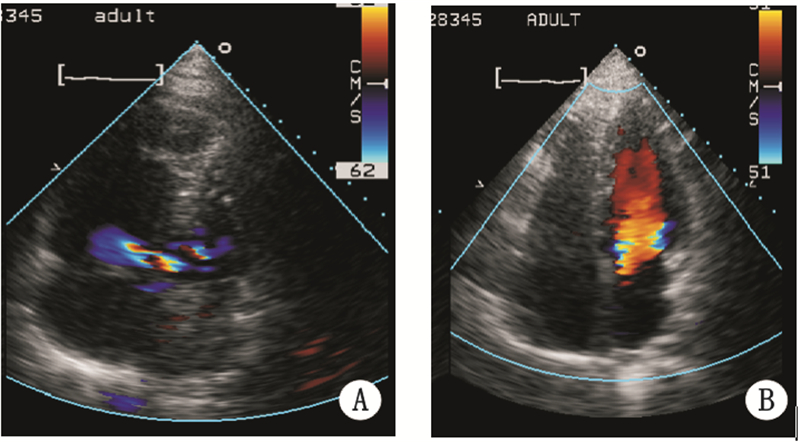

1 资料与方法男,41岁,因活动后胸痛、气短4 d,伴晕厥2次入院。患者近1年间断出现双下肢水肿,3~5 d后可自行消退,未诊治。近1个月偶有双下肢无力、伴麻木。近4天患者活动后出现气短,伴双下肢麻木,休息30 min后症状缓解,无头晕、胸痛,无咳嗽、咳痰。近3天气短伴胸闷、胸痛、大汗,并晕厥2次,约3 min后意识恢复。患者既往体健,否认高血压病、糖尿病史。个人史:货车司机,吸烟20余年,平均40支/d,已戒烟半年;偶饮酒。家族史:父亲1年前因脑梗塞去世;否认高血压、糖尿病、冠心病家族史及其他家族遗传病史。入院查体:体温36.5 ℃,脉搏108次/min,呼吸22次/min,血压104/79 mmHg(1 mmHg=0.133 kPa);双肺呼吸音清晰,双肺未闻及干湿啰音,双侧未闻及胸膜摩擦音。心率108次/min,心律齐,未闻及额外心音,肺动脉瓣听诊区第2心音亢进,其他各瓣膜听诊区未闻及病理性杂音;双下肢感觉异常。入院后急查血气分析示:pH 7.49,PO2 53 mmHg,PCO2 26 mmHg,HCO3- 20 mmol/L,BE-ECF -3.4 mmol/L,BE-B -1.2 mmol/L。化验回报:血浆D-二聚体2.06 mg/L;BNP 966 pg/mL;TnI 0.634 ng/mL。心电图:Ⅱ、Ⅲ、AVF、V1~V5导联T波倒置,AVL导联rS波。胸部CT示左、右肺动脉及以下分支血管内广泛充盈缺损影;右心房室增大。下肢静脉超声示:右侧股浅静脉末端、右腘静脉及小隐静脉内血栓形成。心脏彩超见图 1A。

| A:入院心脏彩超,可见右心房明显扩大,房间隔存在3 mm右向左分流;B:溶栓治疗后5 d心脏彩超,右心房较前明显缩小,心房水平未见分流 图 1 患者心脏彩超结果 |

入院诊断:肺栓塞、急性肺源性心脏病、三尖瓣关闭不全、肺动脉高压(中度)、房间隔缺损、右下肢静脉血栓。治疗经过:给予阿替普酶溶栓治疗,溶栓后给予口服华法林、重叠磺达肝癸钠5 d抗凝治疗及盐酸地尔硫卓。患者症状好转,无胸痛、气短。溶栓后第1天复查血气分析示:pH7.44,PO2 84 mmHg,PCO2 34 mmHg,HCO3- 24 mmol/L,BE-ECF -0.8 mmol/L,BE-B 0.5 mmol/L。溶栓后第5天复查下肢血管超声示:右侧腘静脉及小隐静脉内血栓。胸部CT大血管造影示:右心室稍示增大,左右肺动脉腔内可见不规则形充盈缺损影,病变范围较前有所缩小。溶栓后第12天复查下肢血管超声示双侧股静脉、腘静脉及右侧小隐静脉未见明确异常。溶栓后第1、5、23天复查心脏彩超见表 1和图 1。

肺动脉栓塞为来自静脉系统或右心的血栓阻塞肺动脉或其他分支所致疾病,多伴发血流通道异常,合并多种心脏疾患。本例患者多种PE危险因素并存,结合症状及螺旋CT,急性肺栓塞诊断明确。患者活动后胸痛伴发晕厥,提示已发生严重血流动力学改变,超声示患者肺动脉压升高,心房水平出现右向左分流。溶栓并持续抗凝治疗后,肺动脉压降低,房间隔右向左分流消失,右心房、心室恢复正常大小;追问患者病史,否认先天性心脏病,查体未见患者有体形瘦长、杵状指、面色苍白、活动后气短、生长发育迟缓等典型先天性房间隔缺损体征,考虑继发房间隔缺损。患者深静脉血栓脱落,阻塞肺动脉及其分支引发急性肺栓塞,致肺动脉压力急骤升高,右心室压力升高继发引起右心房压力增加,当右心室压力>右心房压力时,功能性闭合的卵圆孔开放,心房出现右向左分流,右心房静脉血进入体循环。正常右心房压力(3~5 mmHg)小于左心房压力(8~10 mmHg),短暂右心房压力突然升高超过左房压时,类似功能性瓣膜的左侧薄弱的原发隔被推开,出现右向左分流。国内外研究提示,PE常合并血流动力学不稳定[2, 3],当右心室压力急剧升高时,破坏了原有左右心室压力平衡[4];右室压力升高继发引起右房压力增加,改变左右心房平衡关系,但国内外此类病理改变的病例较少[5],多为先天性房间隔缺损合并肺栓塞。值得注意的是,由于PE症状的严重程度有很大差别,合并出现血流通道异常后,如反常性栓塞[6],与其他心肺疾病易混淆,误诊率较高[7],应充分利用肺动脉造影、肺CT、心脏彩超等检查手段,甄别原发病及时予以治疗。